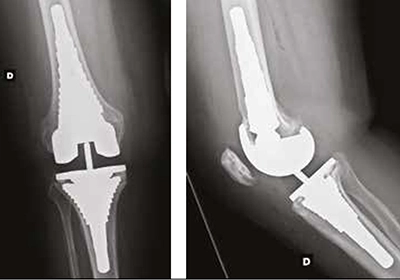

Exemple de reprise de prothèse

Ci-dessous, vous pouvez voir la radio d'une prothèse partielle interne, 12 ans après la pose initiale, avec enfoncement de la pièce tibiale dans le tibia (flèche rouge) et la radio de la prothèse de reprise avec une longue tige.